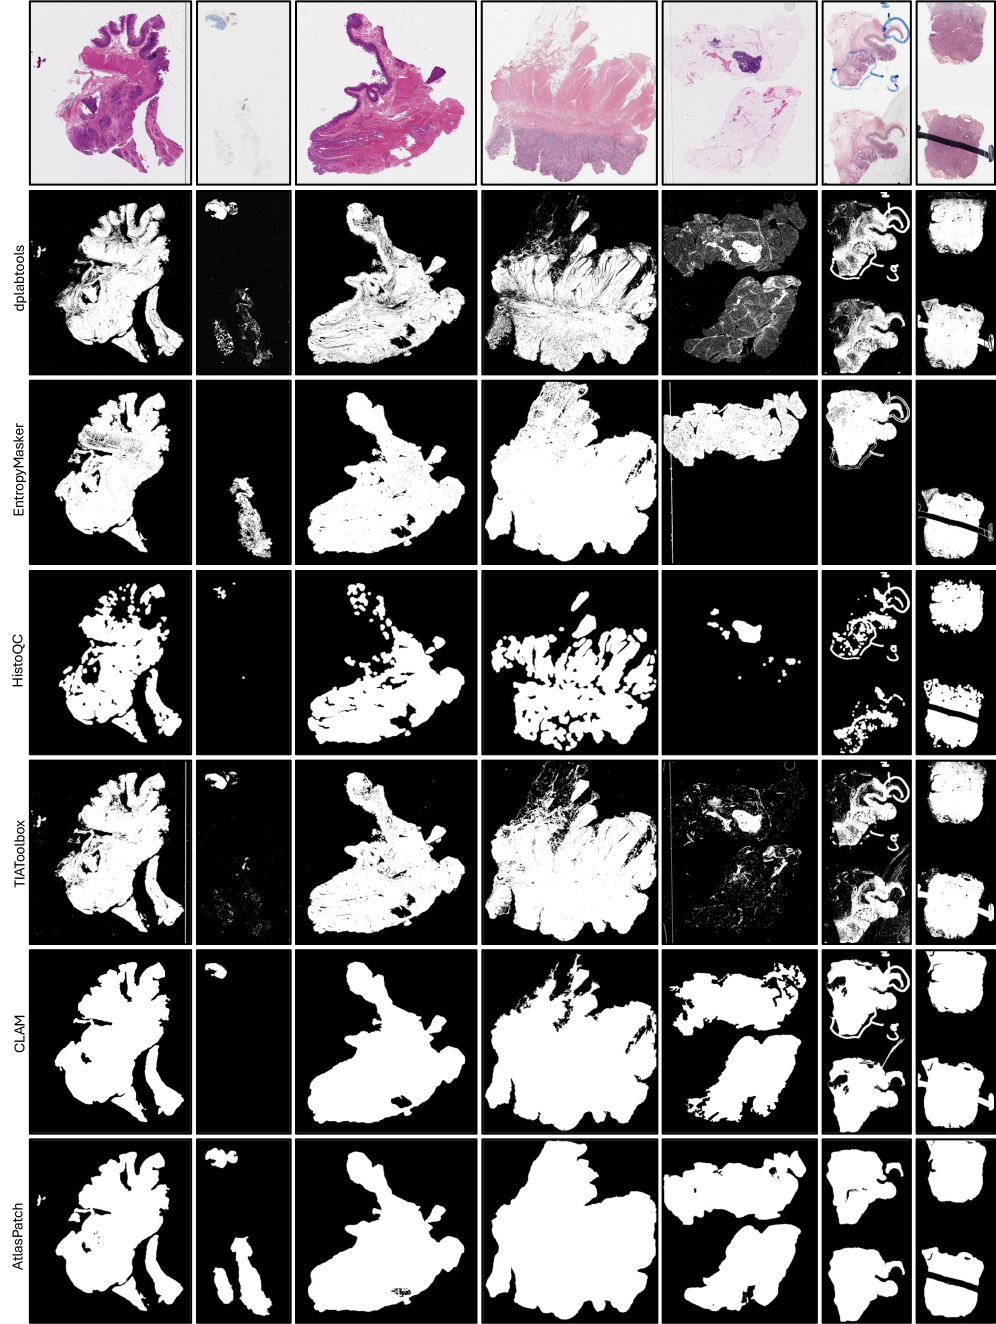

To validate the tissue detector in AtlasPatch, we benchmarked its performance against widely used thresholding-based methods (TIAToolbox [pocock2022tiatoolbox], CLAM [Lu2021CLAM], dplabtools [DPLabPaper], EntropyMasker[EntropyMasker], HistoQC [Janowczyk2019HistoQC]), a zero-shot SAM2 baseline (without finetuning), and recent deep learning–based methods (Trident-GrandQC [weng2024grandqc, Zhang2025Trident], Trident-Hest [Zhang2025Trident]), by showing their predicted masks for the given WSIs. The Trident tool comes with two variants that both operate at the patch-level, with Trident-GrandQC operating on thumbnail patches, while Trident-Hest operating on high magnification (10x) patches. Fig. 4 summarizes these comparisons qualitatively on representative slide thumbnails drawn from diverse organs and tissue conditions (brightness, fragmentation, sparsity, scanner artifacts, and pen markings), and quantitatively using segmentation metrics on a held-out test set and a runtime-performance analysis.

Refer to caption

Figure 4: Quantitative and qualitative analysis of AtlasPatch tissue detection against existing slide-preprocessing tools. Representative WSI thumbnails are shown from diverse tissue features and artifact conditions, with tissue masks predicted by thresholding methods (TIAToolbox, CLAM) and deep learning methods (pretrained ”non-finetuned” SAM2 model, Trident-GrandQC, Trident-Hest, and AtlasPatch), highlighting differences in boundary detection, artifact suppression, and handling of fragmented tissue (more tools are shown in Extended Data Figs. 3-5). Tissue detection performance is also shown on the held-out test set, highlighting that AtlasPatch matches or exceeds the other methods. The segmentation complexity–performance trade-off shows F1-score against segmentation runtime (per 100 WSIs), shows AtlasPatch achieves high performance with substantially lower wall-clock time than patch-based methods, underscoring its suitability for large-scale WSI preprocessing.

Thresholding-based methods show limited robustness to the heterogeneity present in WSIs. Across multiple samples in Fig. 4, CLAM and TIAToolbox can miss substantial tissue when contrast or stain appearance deviates from typical cases (samples 3, 4, and 7), and they frequently fail to distinguish artifacts from tissue (samples 7-9). Consistent with these qualitative observations, we found that the CLAM tool fails to detect any tissue at all in roughly half of the prostate WSIs from the PANDA dataset. The pretrained (non-finetuned) SAM2 model is also not a reliable out-of-the-box tissue detector. Without histopathology domain exposure, it inconsistently captures tissue and can include visually salient non-tissue patterns, reflecting the gap between the generic object detection in SAM2 and the more subtle cues required for robust tissue detection. We notice patch-based deep learning methods offer improved robustness than thresholding-based baselines. However, Trident-GrandQC frequently misinterprets artifacts as tissue, particularly in slides with strong pen markings or scanner streaks. Trident-Hest shows more resilient behavior with respect to artifacts but can miss tissue at ambiguous boundaries (e.g. misses a chunk of tissue in sample 7). While these methods operate at the patch level and are expected to recover fine-grained tissue details, they can lose global context which sometimes could be beneficial to classify ambiguous regions. In contrast, AtlasPatch delivers consistent tissue masks across all the scenarios shown. It accurately outlines tissue in low-contrast slides, preserves small tissue fragments in highly fragmented biopsies and effectively suppresses non-tissue artifacts. While AtlasPatch does not always reproduce every fine-grained internal hole within tissue regions, it systematically captures the full spatial footprint of biologically meaningful tissue and avoids large false negatives.